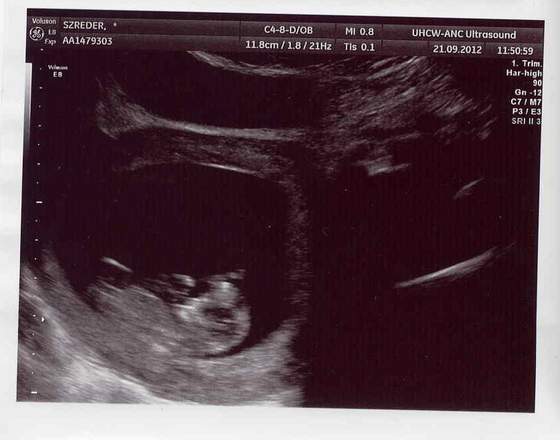

oczywiście jest cudny i cieszę się, że wsio ok i też bym skorzystała z zaproszenia na powtórkę z usg bez dwóch zdań, ale powiedz mi jeszcze elle co to za usg? w sensie, to nie jest 3d chyba nie? to na prenatalnym takie piękne zdjęcia były?

aż ciężko uwierzyć, że to 6 cm człowieczek